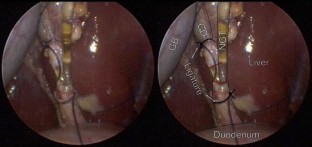

Fig. 1

The laparoscopic cholecystectomy was performed beginning with visualization of Calot’s triangle, and dissection of Calot’s triangle was achieved using a monopolar cautery device. Once the cystic duct was exposed, sealing was performed proximally and distally, and the cystic duct was divided midway using the LVSS. The procedure was completed in the standard fashion.